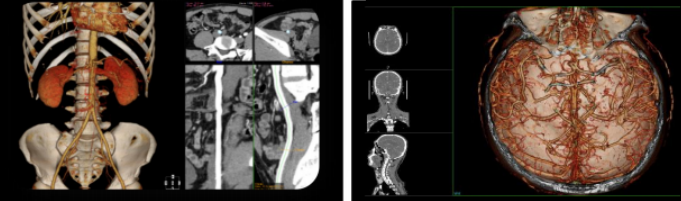

完美的图像质量

肾部三维

• 图像高清,形体完整